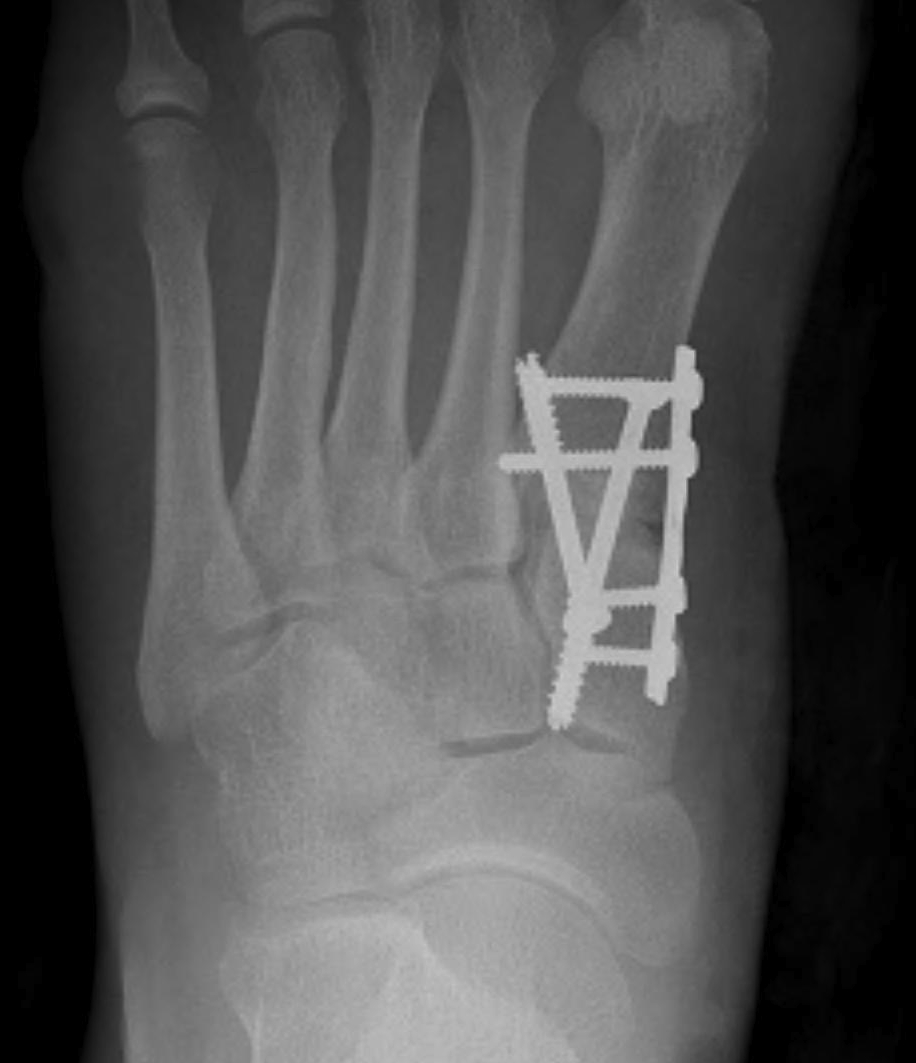

Lapidus procedure

Indications

- hypermobility of the TMT joint

- obliquity of the first TMT joint